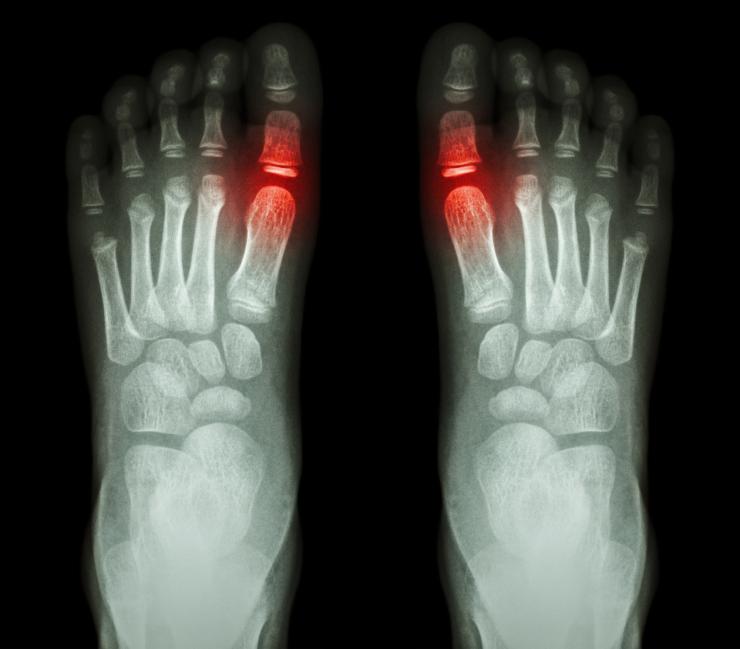

La gota o los ataques de gota se producen cuando la acumulación de cristales de urato —derivada de los altos niveles de ácido úrico en sangre— provoca la inflamación e hinchazón de las articulaciones. Así pues, las partes del cuerpo que más afectadas se ven son: el dedo gordo del pie (uno o ambos), las rodillas, los tobillos, los codos, etc.

• enrojecimiento de la articulación afectada